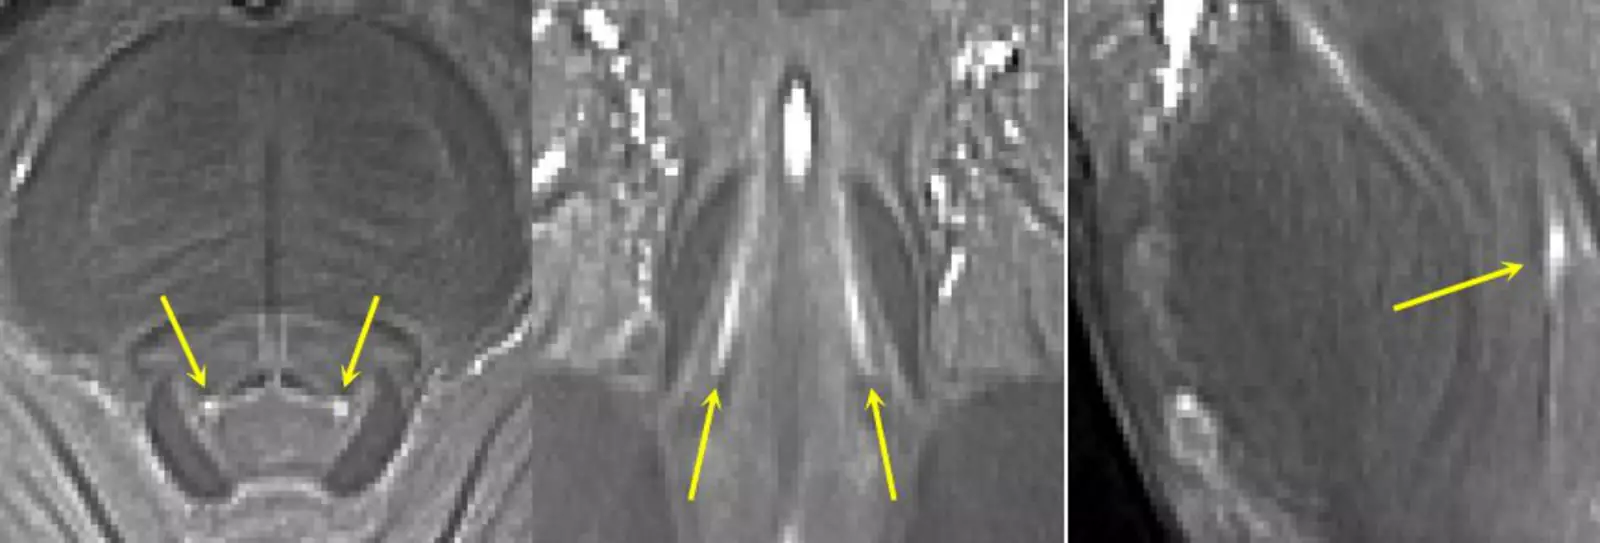

Обычные больничные томографы «не видят» голубое пятно, но с этим хорошо справился новый МРТ-сканер, который обеспечивает разрешение размером с песчинку. Сканер позволил команде изучить голубое пятно испытуемых и подтвердить, что, чем сильнее повреждения этой области, тем тяжелее проявляются симптомы апатии у пациентов.

Голубое пятно на МРТ-сканере 7T.